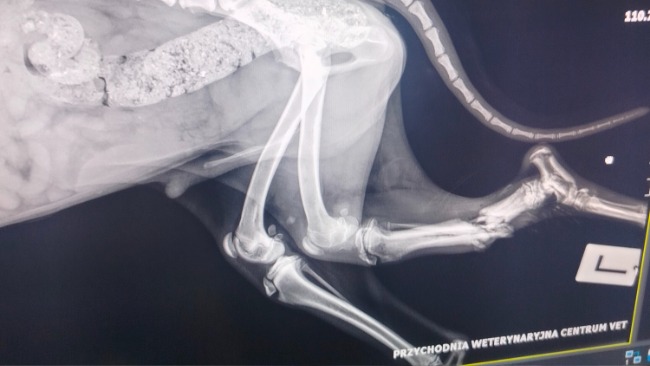

A jego łapa… Otwarte złamanie obu kości.

Dziś lekarze oczyścili ranę, zabezpieczyli kość, dostał silne leki i kroplówki. Ale to dopiero początek drogi.

Ma babeszjozę. Wyniszczenie organizmu. Infekcja jest poważna. Przed nami dni niepewności i decyzji, których nikt nie chce podejmować. Może uda się uratować łapę. Może nie. Ale zrobimy wszystko, żeby uratować jego życie.